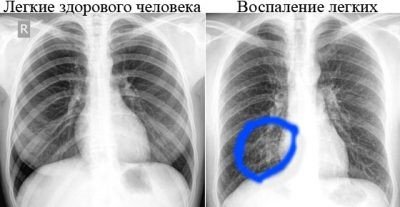

Тень на снимках – это уплотнения, белые участки – это воздух или жидкость. Чтобы получить более точную картину заболевания, рентген назначается в прямой, косой и боковой проекции. Этот диагностический метод дает возможность установить на начальных этапах развития туберкулеза.

Участки тени в легких могут свидетельствовать, как об опасных легочных патологиях, так и о некачественной рентгеновской пленке. Не нужно паниковать, если есть темные пятна на снимке. Эта процедура – дополнительная диагностика, чтобы правильно поставить диагноз, нужно учитывать симптомы и общее состояние человека.

Рентгенологи используют разную классификацию затемнений. Определяются размеры, участок расположения, геометрическая форма. К примеру, треугольные пятна могут говорить о плеврите либо ателектазе. Пятна бывают тотальными, очаговыми, сегментарными, субтотальными. Локализация может быть легочной или внелегочной.

Тень дают любые виды новообразований. Если определяется уплотнение, это признак воспалительного процесса. Внелегочная тень указывает на наличие жидкости, аневризмы, лимфоденита, опухоли позвоночника или пищевода. Чтобы поставить точный диагноз, нужны дополнительные обследования, визуальный осмотр.